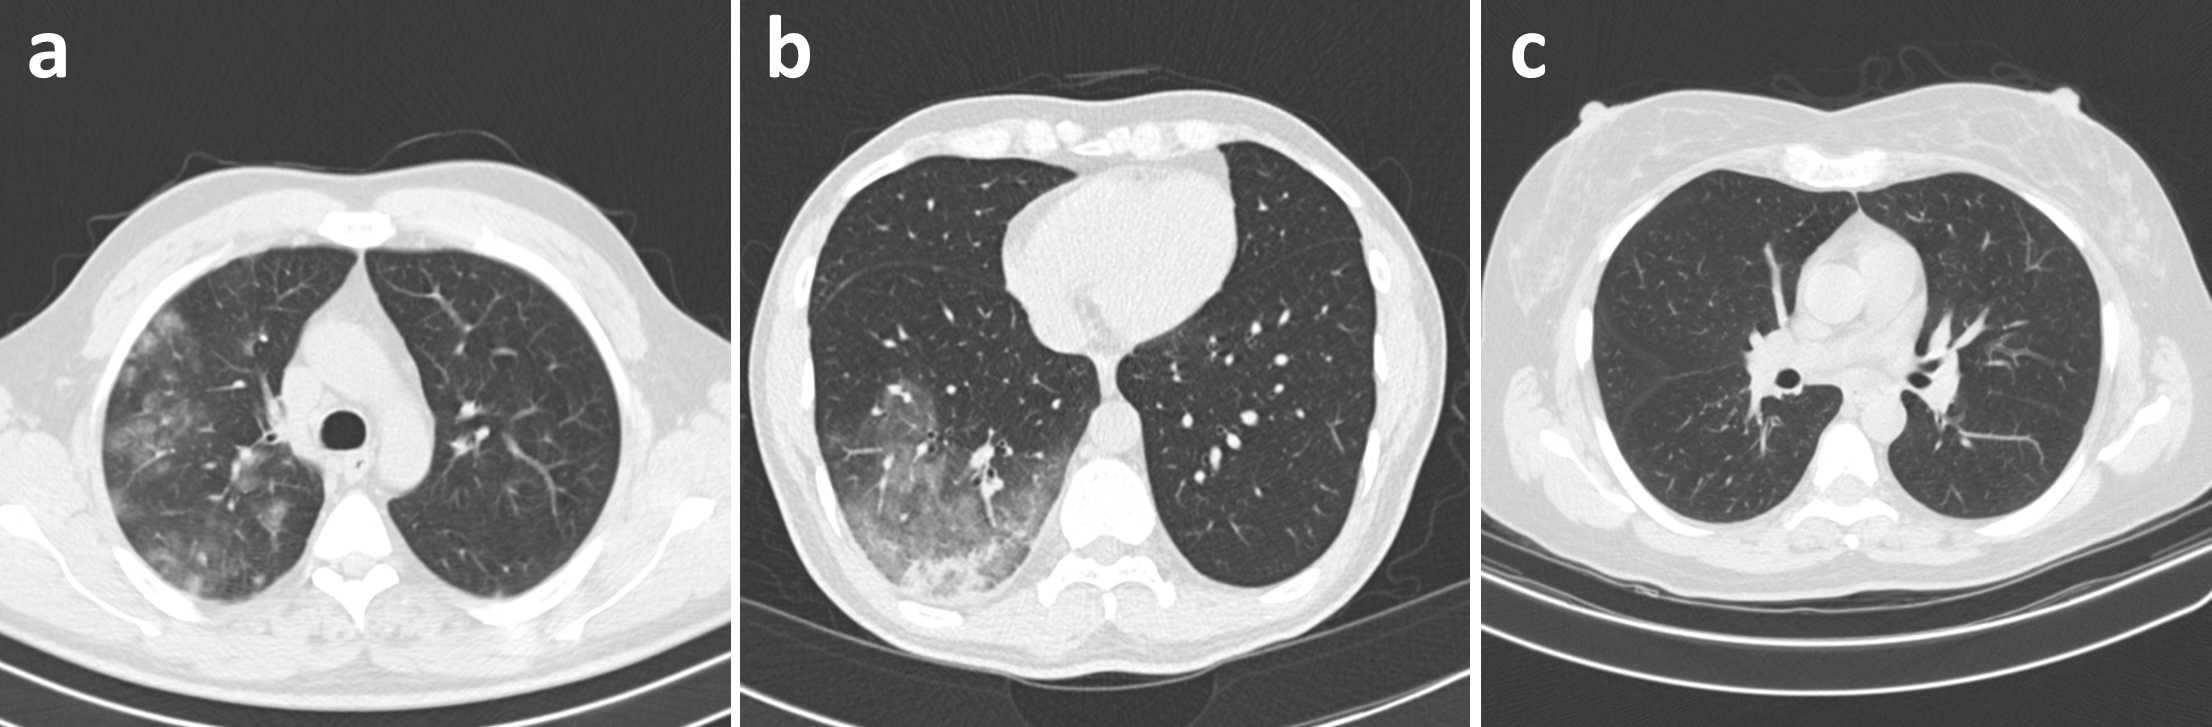

Figure 1: Example chest CT images from the COVIDx CT-3 dataset. (a) a COVID-19 case, (b) a CAP case, (c) a normal control.

Each patient is associated with one of three possible infection types: (a) COVID-19, (b) community-acquired pneumonia (CAP), or (c) normal controls, with Figure 1 illustrating an example of each infection type. For CT volumes which were not labelled at the image level, labels were obtained in one of three ways: (1) segmentation-based labelling, where ground-truth infection masks were used to identify abnormal CT slices, (2) non-expert manual labelling, where non-experts manually labelled CT slices with obvious abnormalities, or (3) model-based automatic labelling, where a pre-trained model [14] was used to identify CT slices with high CAP or COVID-19 confidence. For all three methods, the selected CT slices were assigned the same labels as their respective patients.